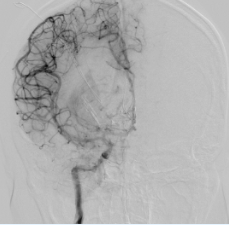

▲急诊头颅CT正侧位图显示患者颅内大量出血

患者病情危急,行急诊手术前须完成一些关键必要的检查如头颅CT扫描等。为提高效率,专家们充分利用送检时间同步会诊。当患者被送进手术室时,最可行的手术方案和目标正好出炉:神经外科开颅血肿清除减压术和产科剖宫产术同时同台进行,麻醉科、手术室和新生儿科在手术室全程充分协作、监护和保障,重症医学科随时做好该孕产妇围手术期各种应急处置准备。